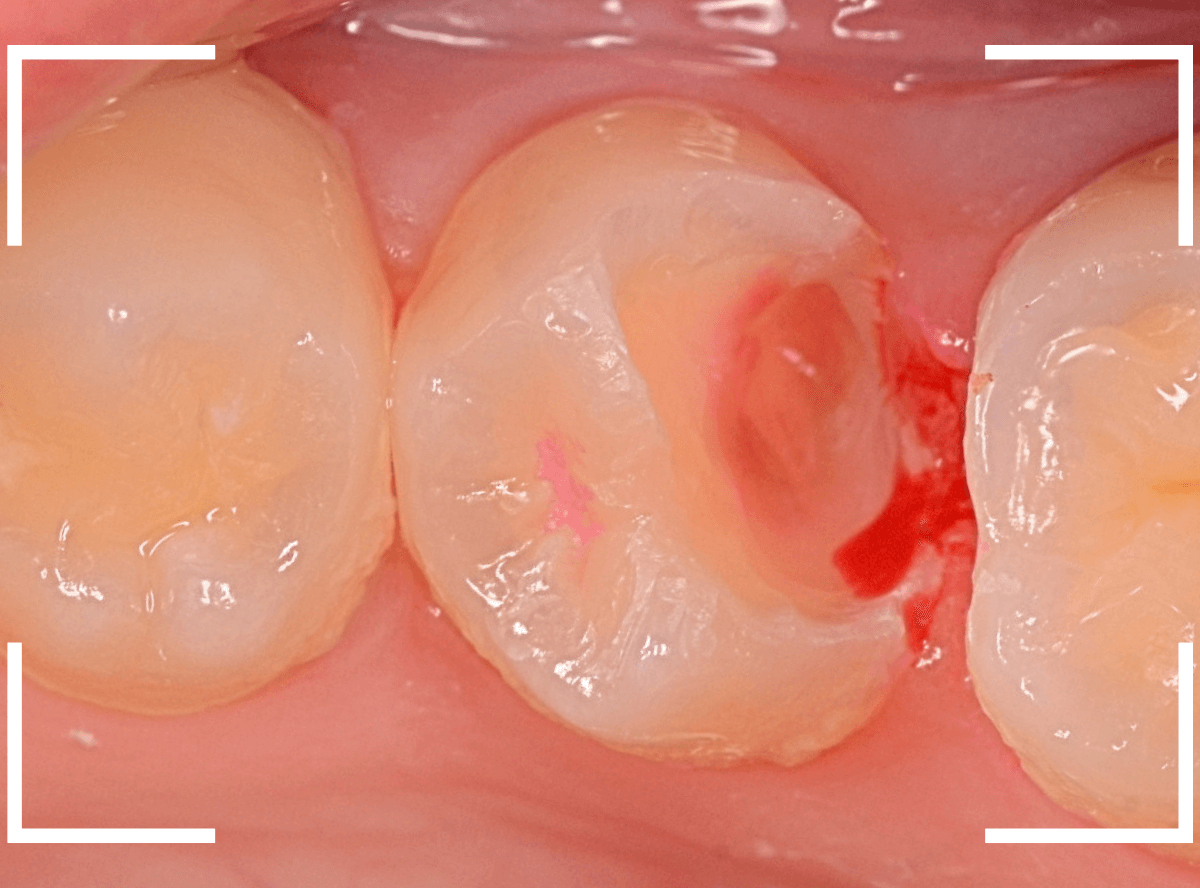

Case.22 痛みはないけど、歯のすきまから大きな虫歯

上の小臼歯の間が虫歯になっていた患者さんです。

症状はありませんし、見た目からも虫歯があるかはわかりませんでした。

治療を開始します。

少し削ると、中からすぐに虫歯が出てきました。

ある程度、虫歯を除去したところで、う蝕検知液で確認します。

赤く染まっている部分が虫歯です。

まだまだ虫歯が中で残っている状況で、かなり深い虫歯なのが確認できます。

全ての虫歯を除去しました。

レントゲン写真からある程度確認出来ましたが、歯の神経スレスレまで虫歯が進行していました。

ここまで虫歯が進行していても、全く症状を感じない事も多いです。